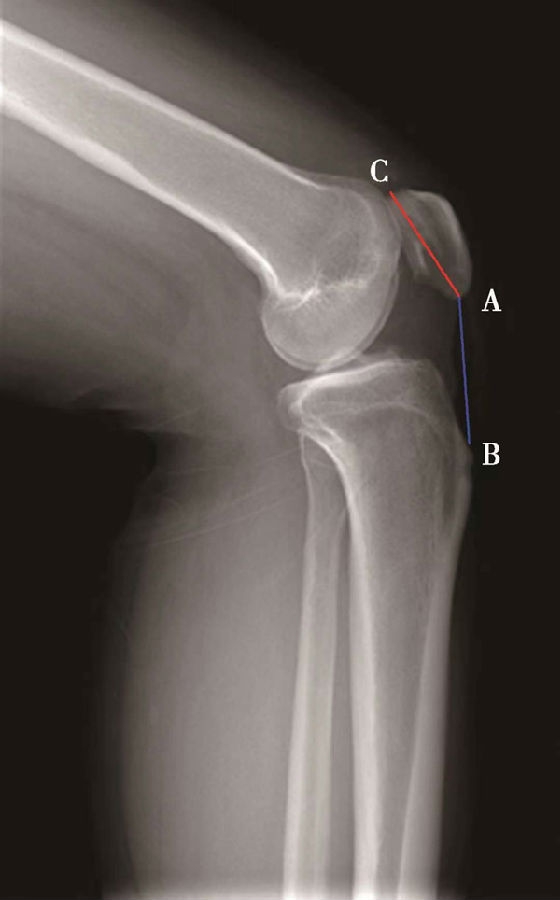

(2)Insall-Salvati指数>1.2意味着高位髌骨(图5),<0.8意味着低位髌骨(图6)。

体位:侧卧位屈膝20°~70°。

如图示:AB是髌韧带长度,AC髌骨纵轴长度。Insall-Salvati指数=AB/AC(图4)。

图4 Insall-Salvati指数 =AB/AC=1.10,为正常髌骨高度

图5 Insall-Salvati指数=AB/AC=1.40,为高位髌骨

但是此法测量髌骨韧带时往往依赖准确的估计胫骨结节与髌骨下极的位置。因此,髌骨下极和胫骨结节的病变都会影响测量的结果,尤其是发生胫骨结节骨软骨炎的患者确定这一位置便更加的困难。此外,该指数不能用于评估胫骨结节向近端或远端移位的效果。因为该指数测量所使用的标记在胫骨结节术后均未发生改变,Insall指数也就不会变化。